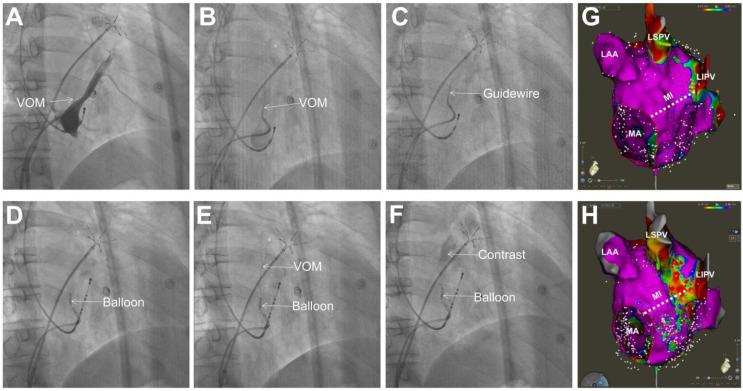

Catheter ablation for persistent atrial fibrillation (PeAF) is particularly challenging, as the clinical outcomes are modest. Pulmonary vein isolation (PVI) plus linear ablation is one of the main strategies for PeAF ablation. Completely durable transmural lesions are difficult to achieve by catheter ablation during mitral isthmus ablation. The ligament of Marshall contains the vein of Marshall (VOM), myocardial tracts and innervation, and serves as arrhythmogenic foci that make it an attractive target in catheter ablation of atrial fibrillation. Additionally, it co-localizes with the mitral isthmus, and may serve as a part of the perimitral isthmus reentrant circuit. Ethanol infusion into the VOM results in rapid ablation of the neighboring myocardium and its innervation. Its incorporation into PVI significantly increases the success rate of mitral isthmus block and the clinical outcome of PeAF ablation.

持续性心房颤动(PeAF)的导管消融术极具挑战性,因为临床效果一般。肺静脉隔离(PVI)加线性消融是PeAF消融的主要策略之一。在二尖瓣峡部消融过程中,通过导管消融很难实现完全持久的透壁损伤。Marshall韧带包含Marshall静脉(VOM)、心肌束和神经支配,是致心律失常灶,使其成为心房颤动导管消融中一个有吸引力的靶点。此外,它与二尖瓣峡部共定位,可能是二尖瓣峡部折返环的一部分。向VOM注入乙醇可快速消融邻近心肌及其神经支配。将其纳入PVI可显著提高二尖瓣峡部阻滞的成功率和PeAF消融的临床效果。